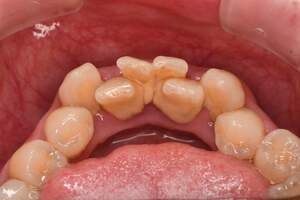

歯石除去

治療前

治療後

| 年齢 | 31歳・女性 |

| 主訴 | 主訴:歯石除去 部位:全顎 |

| 治療内容 | 初診検査・歯石除去 |

| 治療期間 | 2週間 |

| 費用 | 合計:約4,000~5,000円 内訳 初診料:約3,000~4,000円 (保険診療) 歯石除去:約1,000円 (2023年1月現在) |

| リスク・副作用 | ・歯肉の炎症がある場合は歯石除去中に出血を伴う可能性があります。 ・処置後に歯がしみることがあります。 ・歯茎の炎症が軽減すると歯茎が引き締まり、歯が長く見えることがあります。 |

| 治療方針 | 前歯部に叢生(歯列不正)があり多量の歯石が認められました。炎症の抑制を優先するため初診時はTBIのみ行い、2回目以降で歯石除去を行いました。今後は縁下歯石(歯ぐきの中に付着する歯石)の除去を全顎的に行っていく予定です。 |

| 担当者所見 | 叢生(そうせい)とは歯が折り重なるようにデコボコにはえている状態をいいます。歯ブラシが難しく磨き残しをしやすい為、普段使用している歯ブラシに加えワンタフトという細かい部分も磨くことのできる小さな毛束の歯ブラシの使用をおすすめしました。 |

| 担当者所見 | 歯石の存在は感じていたものの歯科医院に苦手意識が強く3年ほど放置していたとのことでした。 舌で触った時にザラザラすることや口臭も気になった為、今回意を決してご来院くださいました。 ブラッシング指導を熱心に聞いてくださり、セルフケアで歯肉の炎症を抑えた上で歯石除去ができたのでお痛みが少なく行えました。 患者様も苦手意識が克服できたと喜んでくださり、今後の治療にも積極的な姿勢です。 |